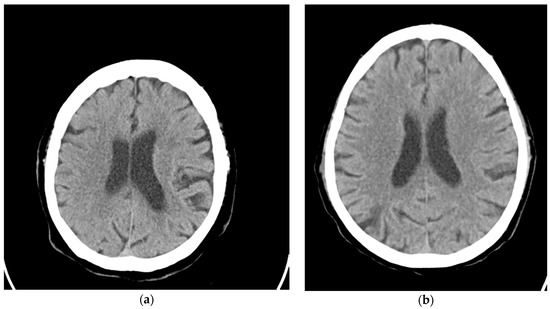

2. Materials and Methods

3.1. Asymmetric Interpretation